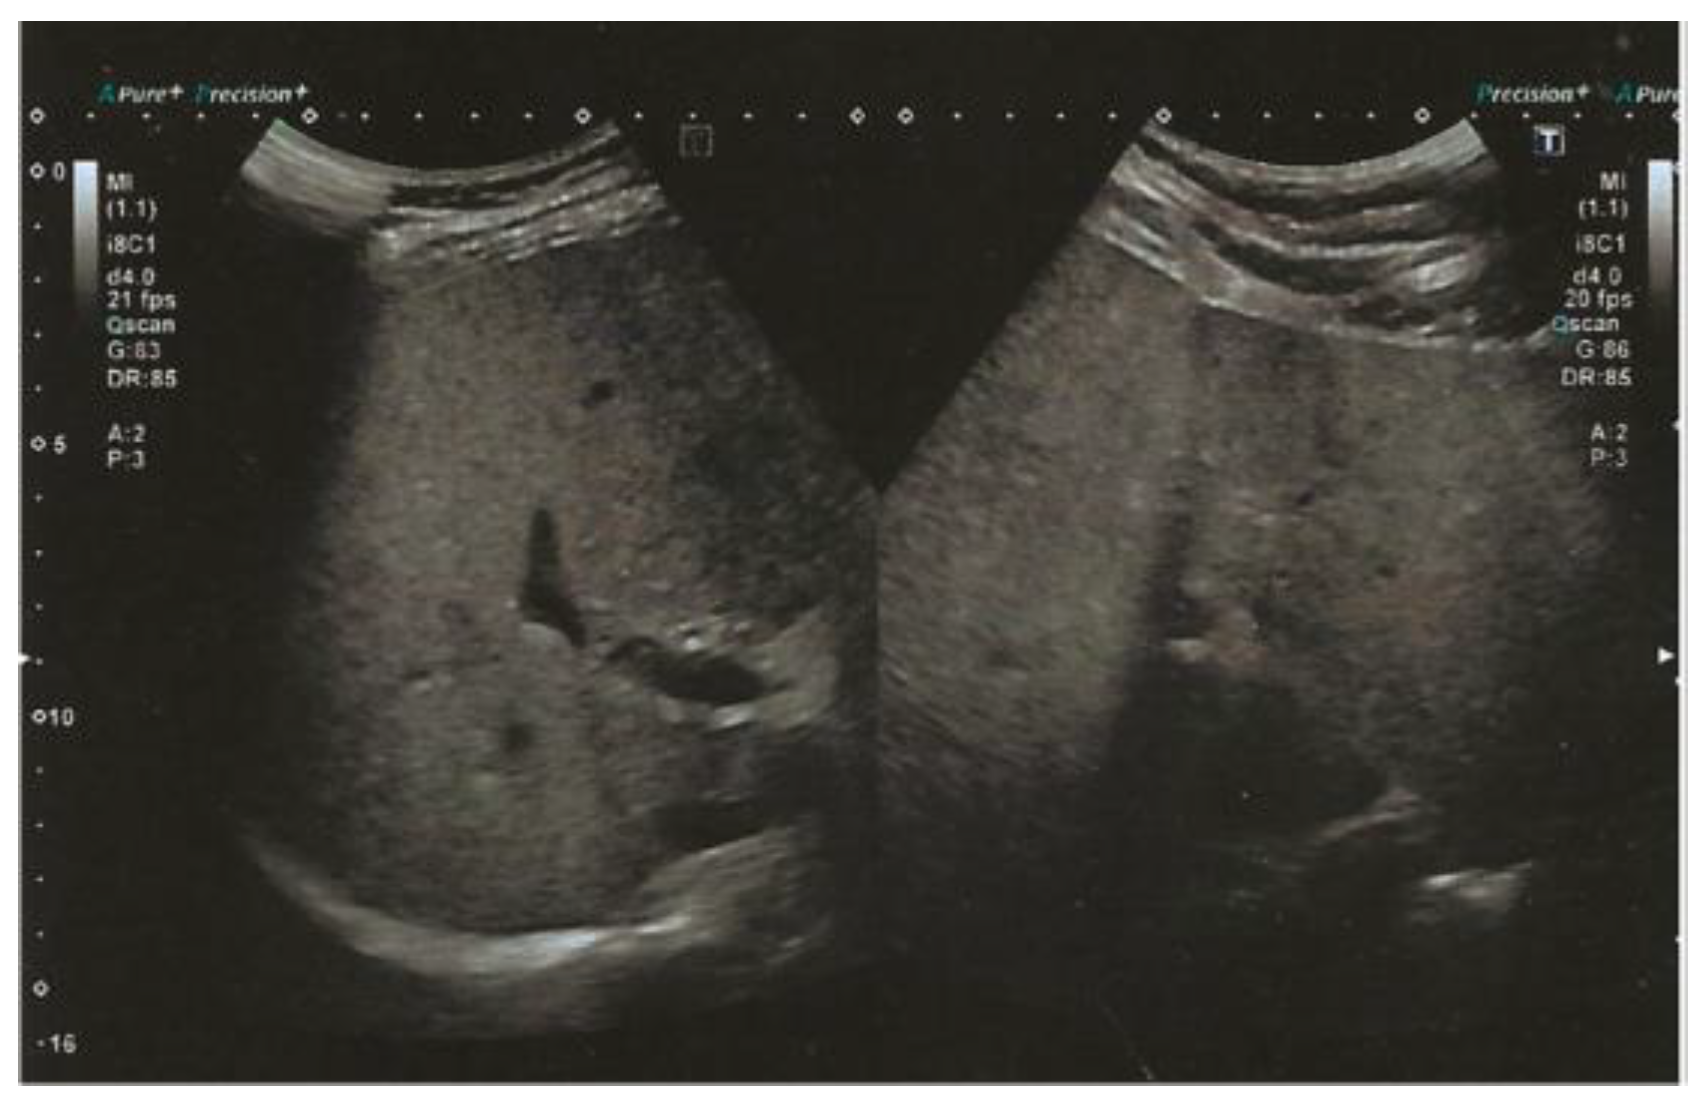

| SLD | Moderate SLD | Yes |